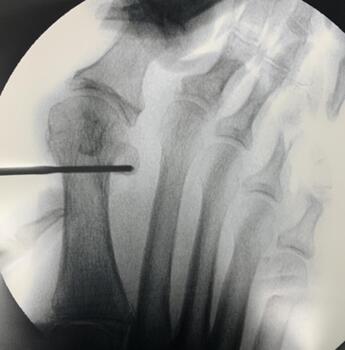

Metatarsal Head Translation. First, shift the metatarsal head laterally by inserting an elevator or hemostat (see third photo above) into the medullary canal. Maintaining the elevator or hemostat parallel to the long axis of the first metatarsal during the shift will prevent deviation of the capital fragment in the sagittal plane.